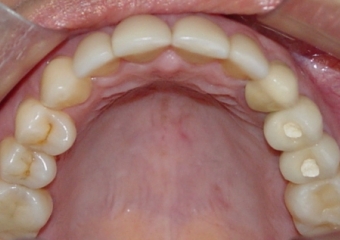

Imagens após o enxerto ósseo

Próteses fixas de porcelana instaladas